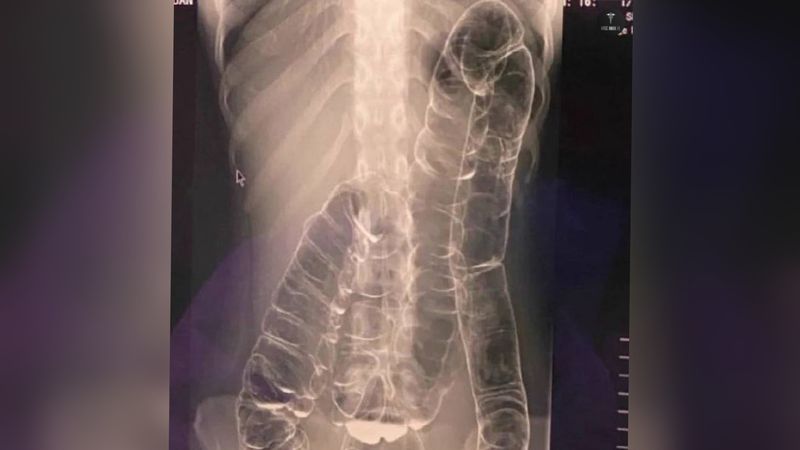

Viral penampakan rontgen usus naik ke dada yang dinarasikan tak buang air besar (BAB) selama satu bulan. Saat ditelusuri, foto rontgen tersebut berasal dari kasus pasien di Taiwan dan sempat ramai pada 2020 lalu.

"Seorang pasien dengan keluhan tidak biasa BAB 1 bulan, apa yang kalian lihat?" demikian narasi viral yang menunjukkan penampakan rontgen, diunggah @BaseAnak**, seperti dilihat detikcom Jumat (29/9/2023).

Akibat kondisinya itu, ia memutuskan pergi ke dokter. Setelah diperiksa, ternyata wanita tersebut mengalami pergeseran usus besar.

"Usus besar saya sangat panjang dan memanjang hingga ke atas," ceritanya.

Dari hasil rontgen menunjukkan bagian terakhir dari usus besarnya tidak memiliki kerutan. Hal ini diduga karena penumpukan kotoran selama bertahun-tahun.

"Sepertinya satu-satunya cara untuk mengatasi masalah ini adalah dengan mengangkat seluruh usus besar saya, namun saya sangat takut. Saya takut akan terjadi komplikasi," katanya.